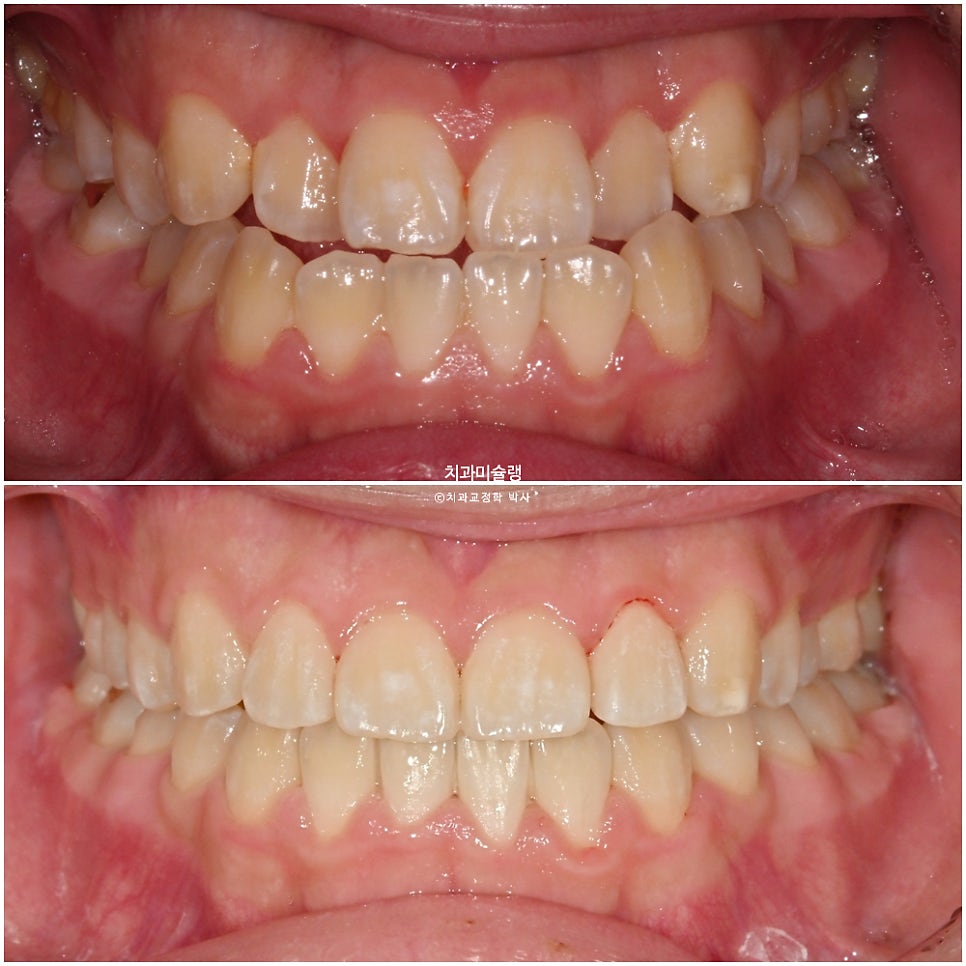

양악수술이 필요한 골격성 3급 부정교합에서 양악수술이나 발치 없이 교정만으로 정상교합을 만드는걸 절충치료 라고 합니다.

오늘은 지난번에 보여드린 주걱턱 비수술 비발치 교정과 비슷한 케이스를 리뷰해보겠습니다.

성장기가 아닌이상 턱 사이즈를 양악수술 없이 조절하긴 불가능하죠.

절충치료의 목표는 큰 아래턱을 작게 만드는게 아닙니다.

하지만 치아를 움직여 최소한 교합만은 정상화 시켜줄 수 있습니다. 단 턱뼈 사이즈의 부조화를 놔둔채 교합을 맞추면 앞니 각도의 한계는 존재하는데 이부분에 대해 잘 봐주시면 좋습니다.

또한 정상교합이 되는것 만으로도 외모가 어느정도 개선되는지 함께 봐주시면 좋습니다.

환자분은 양악수술을 절대 원치 않아, 교정만 하기로 했습니다.

아래 전체 치열을 교정용 나사를 이용하여 발치없이 사랑니 공간으로 이동시키는 비발치 치료계획 입니다.

교정용 나사를 이용하여 전체치열 후방이동을 지속하다가 치료시작 1년 11개월차, 교정치료를 마무리 했습니다.

턱뼈가 어긋난 상태에서 교정만으로 앞니 교합을 맞추면 위 앞니는 정상각도보다는 더 커지며 처음보다 좀더 뻗치게 됩니다. 또 아래앞니는 정상보다 더 뒤로 누운 각도가 될수밖에 없습니다.

이부분에 대해 허용한다면, 양악수술이나 발치 없이도 주걱턱 부정교합에서 교정만으로 좋은 결과가 나옵니다.